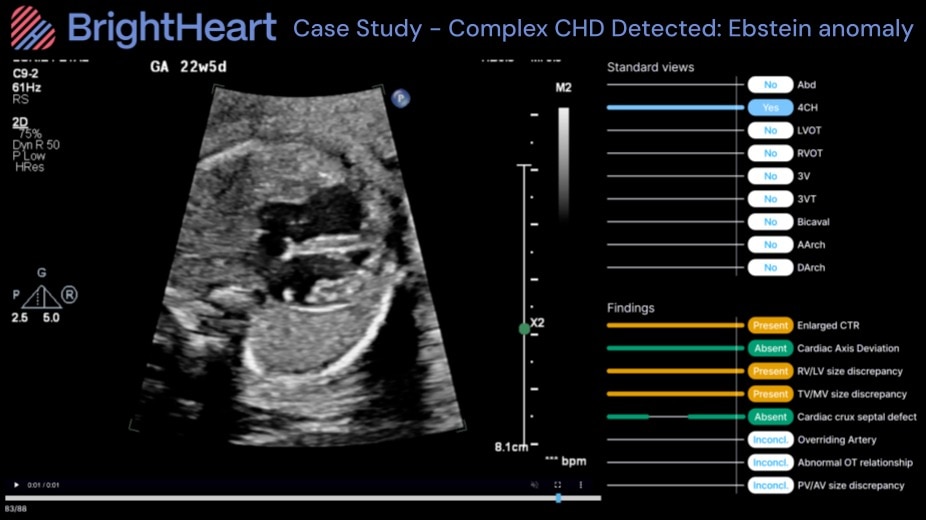

B-Right Screen: Expert-Level Fetal Heart Evaluation for CHD Screening.

- The ultimate screening tool delivering AI-powered analysis of 8 key structural markers to quickly identify or confidently rule out signs of severe CHD

- 98.7% sensitivity for detecting severe CHD indicators and 97.7% specificity in confirming normality among conclusive cases- supporting clear, confident decisions, and better care